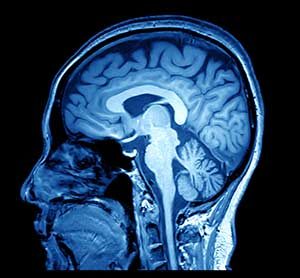

Der Hirnschädel lässt sich als beständige Hülle rundum das Gehirn beschreiben.

Mittels Röntgenstrahlen werden während einer Computertomografie – kurz CT – detailgenaue Querschnittsbilder des Menschen erstellt. Inzwischen können auf diese Weise bis auf einen Millimeter genau, Abweichungen der Dichte eines jeden Organs festgestellt werden.

Ohne Operationen werden dem Mediziner die Organe direkt sichtbar gemacht, sodass erste Diagnosen möglich sind. Dabei gehört die Kraniale Computertomografie – also ein CT des Kopfes – mittlerweile zu den wichtigsten Anwendungsgebieten. Denn nebst Blutungen, verdächtigen Erweiterungen von Hirnarterien, Gehirnödemen, vermuteten Schlaganfall können so auch eventuelle Schädelbrüche genauer unter die Lupe genommen werden.